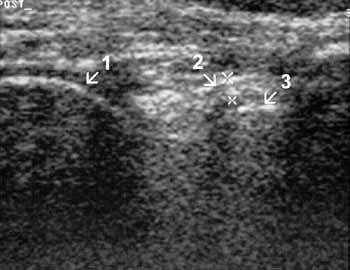

Рис. 13. Коленный сустав в норме. Задняя поверхность сагиттальная проекция.

1 — медиальный мыщелок, 2 (+) — задняя крестовидная связка, 3 — большеберцовая

кость.